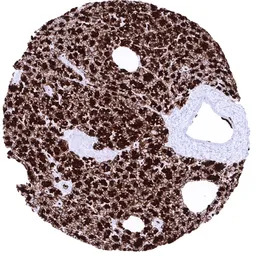

IHC-P analysis of human pancreatic acinar cell carcinoma tissue section using GTX04436 GP2 antibody [MSVA-475M] HistoMAX.

Acinar cell carcinoma showing strong GP 2 immunostaining of all tumor cells.